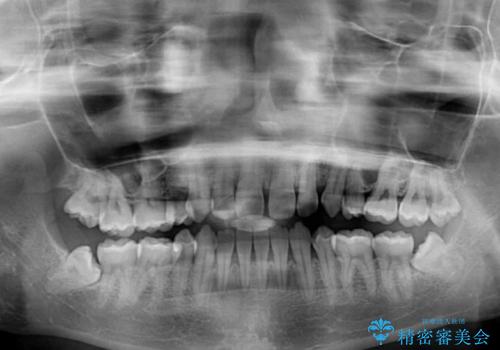

- 以前の矯正治療の後戻りにより、上の前歯にスペースができたことを気にして来院された患者様です。

インビザラインを用いて前歯のスペースを閉じつつ、上下の咬み合わせを構築していくこととしました。